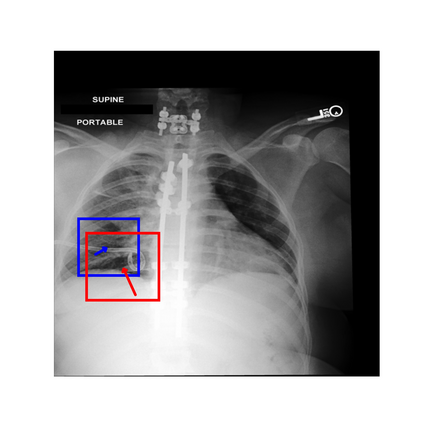

To address these issues, we propose a novel Adaptive patch-word Matching (AdaMatch) model to correlate chest X-ray (CXR) image regions with words in medical reports and apply it to CXR-report generation to provide explainability for the generation process. AdaMatch exploits the fine-grained relation between adaptive patches and words to provide explanations of specific image regions with corresponding words. To capture the abnormal regions of varying sizes and positions, we introduce the Adaptive Patch extraction (AdaPatch) module to acquire the adaptive patches for these regions adaptively. In order to provide explicit explainability for CXR-report generation task, we propose an AdaMatch-based bidirectional large language model for Cyclic CXR-report generation (AdaMatch-Cyclic). It employs the AdaMatch to obtain the keywords for CXR images and `keypatches' for medical reports as hints to guide CXR-report generation. Extensive experiments on two publicly available CXR datasets prove the effectiveness of our method and its superior performance to existing methods.